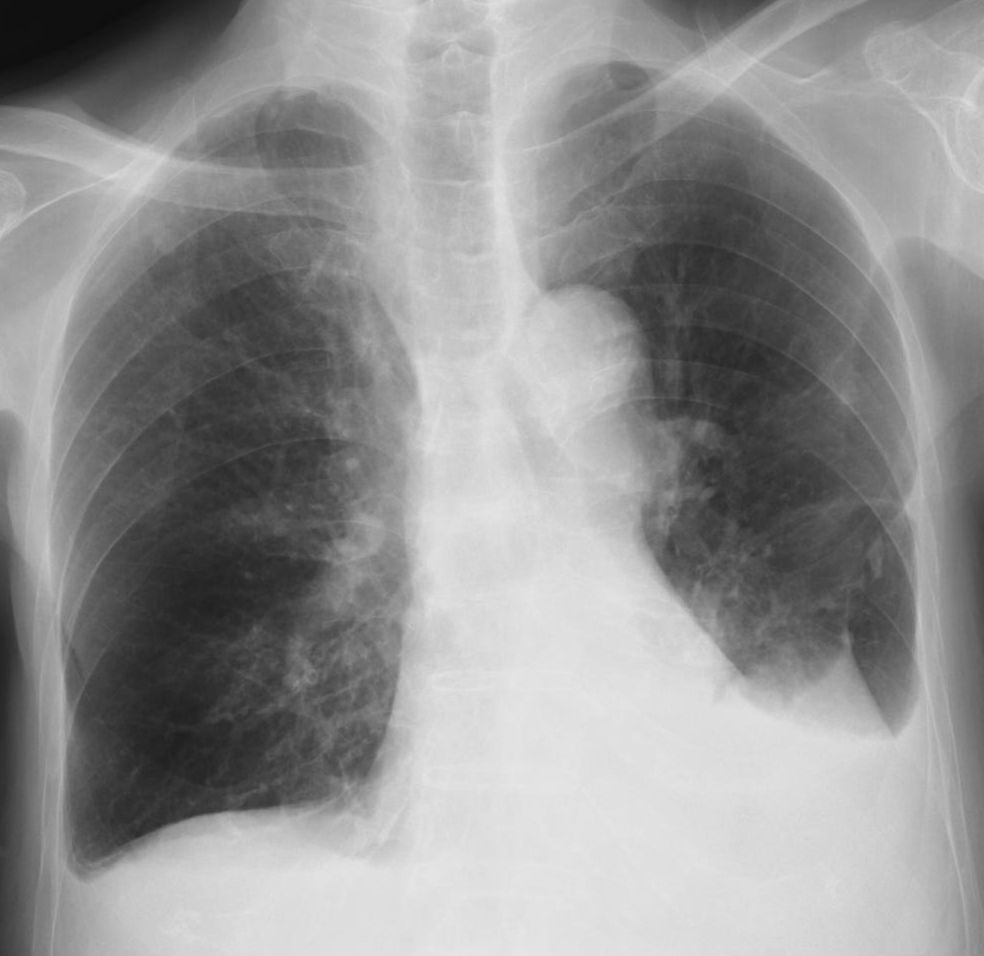

気道分泌物の閉塞によるものと思われる無気肺の存在 がある、(3)胸部画像上、肺硬化像を伴った肺炎など の肺病変の存在がある、以上のようなときに、ポジショ ニングの適応があると言える。 ただし、すべての患者においてポジショニングを実施 無気肺になる原因は、痰詰まり・気管支内の異物・肺がんが多いです。 主な症状は発熱・息切れ・頻脈などです。 聴診や画像検査(胸部レントゲン検査や胸部CT検査)を用いて診断します。 特に肺がんや気道内異物が疑われる場合は、気管支内視鏡を無気肺の存在診断は、画像検査で、含気を失った罹患肺葉は濃厚なくさび型陰影として認められる。典型的な肺葉性無気肺の場合、図に示したような所見をとる( 図表 > 図表 > 図表 > 図表 > 図表 > 図表 > )。 。 また、無気肺によって生じる位置の偏位や濃度の変化を来す無気肺周辺の変化を

>画像所見 : Chest Xp : 右上葉に強い閉塞性の変化(無気肺と閉塞性肺臓炎)がみられ、肺門部にも腫瘤影が疑える(↑)。 造影CT : 右上幹は腫瘍で閉塞し、気管および気管支周囲のリンパ節も腫大無気肺は、肺の一部または全体に空気がなく、肺がつぶれた状態です。 無気肺の一般的な原因は気管支の閉塞です。 酸素レベルが低くなる、または肺炎が起こると、息切れが生じます。 診断を確定するには胸部X線検査を使います。 治療では、深い呼吸>画像所見 : 胸部単純 x 線写真正面像では右下肺内側が暗くなっており、右心第 2 弓の輪郭が不明瞭(シルエットアウト)。 側面像では肺門部から前肋横角に向かう紡錘形の陰影(↓)がみられる。 >診断 : 中葉無気肺 >解説 : 無気肺化した中葉は正面単純写真では右心第 2 弓を底辺と

•初期の肺門部型肺癌は、画像上指摘困難 •閉塞性肺炎や無気肺などの末梢肺の二次 性変化が手がかりとなることが多い •小細胞癌は、末梢肺の二次性変化が乏しい 傾向にある •喫煙、重金属、石綿、珪素、大気汚染などと の関連が高い 画像の特徴としては ①無気肺になった側の肺が真っ白になる。 ②縮んだ肺は容積が減少する。 ③肺の縮みの程度(抜けた空気の程度)が大きいと、周りの組織が引っ張り込まれる。 肺内の空気が抜けてしまうわけですから、肺の濃度は真っ白になります。 無気肺が疑われる場合、画像検査と気管支検査を実施して診断します。 画像検査 胸部レントゲンやctなどの画像検査が行われます。 一般的には、無気肺となった肺は濃厚な楔状の陰影として見られます。

胸水と無気肺のx線画像の鑑別 無気肺 胸水 透過性低下部分が胸壁に接する部位の方向 下(尾側)に向かう 出典:106f28 上(頭側)に向かう 出典 理由 液体だから•上肺静脈、右肺動脈下幹 –肺門血管の太さ •中間気管支幹の葉間肺動脈の太さは、約15mm •通常、交差する後部の肋骨の幅に近似 •肺野 –上下の肺血管陰影の密度の差 •正常の上下比は、1:152 •横隔膜 –高さは、右>左肺浸潤をきたし確定診断に難渋した悪性リンパ腫の2例 肥田 典子a a堀内 一哉 a石井 源 笠原 慶太a a鈴木 隆 b御子神哲也 要旨:初診時より肺病変を伴う悪性リンパ腫の報告は少なく,画像所見も多彩であるため確定診断までに難